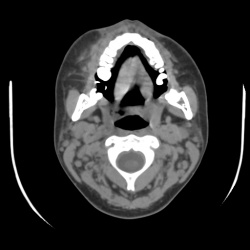

Коллеги прошу помочь разобраться с данным случаем. Молодая девочка 24 года. Поступила с жалобами на боли в области лица,субфебрильная температура. Выполняли СКТ пазух в другом мед. учереждении,...